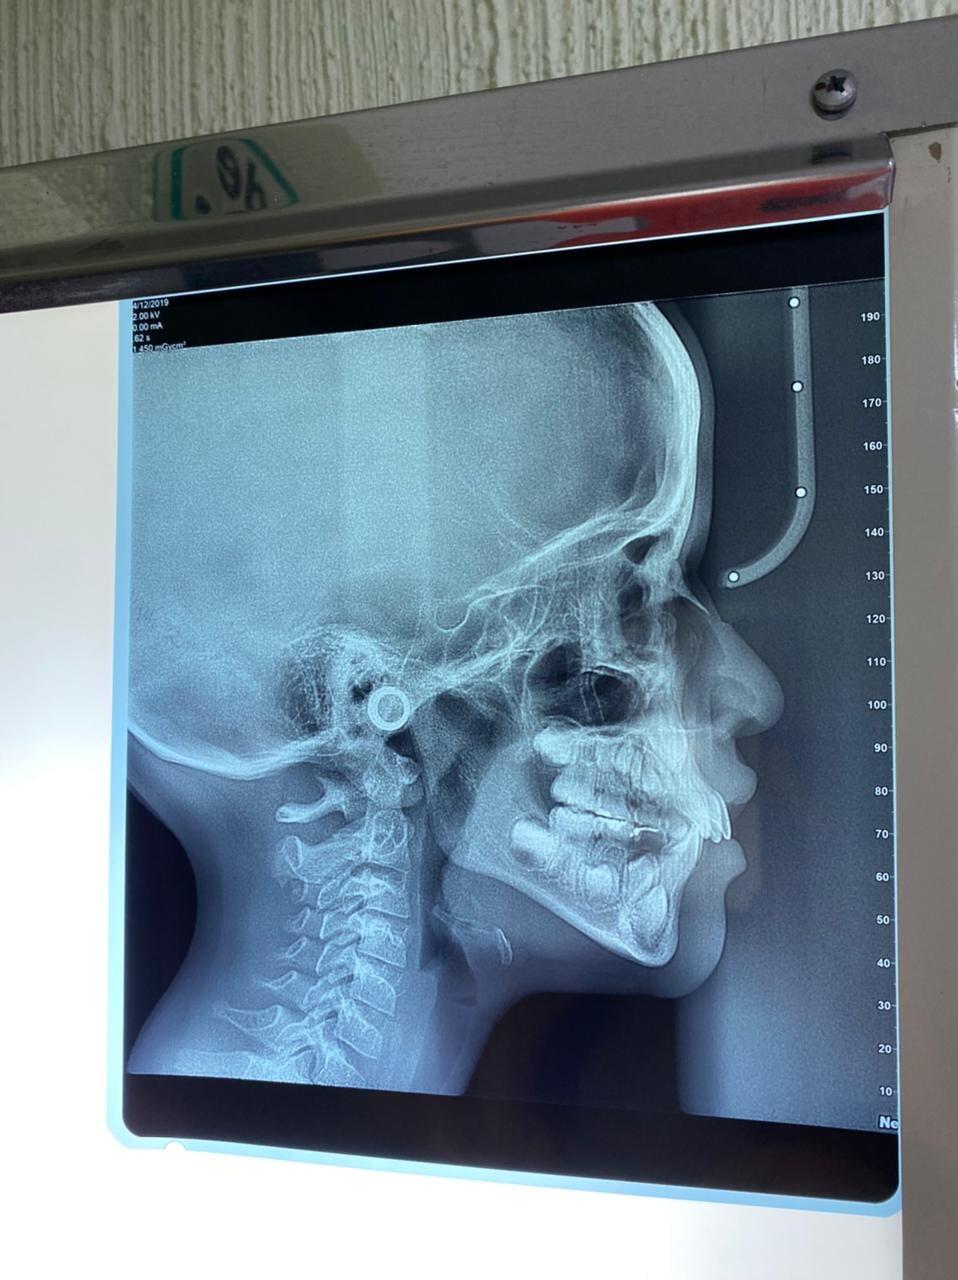

La mejor forma de conocer si tus dientes necesitan un tratamiento ortodóncico es agendar una consulta con nuestros especialistas para realizar el diagnostico correspondiente. A través del diagnóstico obtendremos elementos indispensables para determinar el tipo de tratamiento, duración y consideraciones generales como la historia clínica y odontológica del paciente, la realización de modelos en yeso de los dientes, radiografías y fotografías. En función de los resultados que arroje el estudio, desarrollaremos un plan de tratamiento de acuerdo con tus características y necesidades.